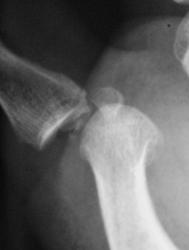

Катенёв Валенти... Дата публикации 01.05.2009, 12:06 Пациент направлен хирургом с диагнозом "перелом". Произвели рентгенографи. Вопрос заключается в том, что данное состояние должно быть обозначено, как "вывих" или "переломовывих"? Пт, 01/05/2009 - 12:46 #1 flagman Не на сайте Был на сайте: 11 лет 5 месяцев назад Зарегистрирован: 05.06.2008 - 20:08 Публикации: 83 а если перелом, вывих. Пт, 01/05/2009 - 12:48 #2 Катенёв Валенти... Не на сайте Был на сайте: 7 лет 4 недели назад Зарегистрирован: 22.03.2008 - 22:15 Публикации: 54876 Спасибо за высказанное мнение. Пт, 01/05/2009 - 13:58 #3 Ермолаев Не на сайте Был на сайте: 8 лет 10 месяцев назад Зарегистрирован: 07.02.2009 - 16:33 Публикации: 670 Валентин Львович! Мое мнение, что имеется вывих и перелом. Два разных костно-травматических изменения с точки зрения патологической анатомии. dok Пт, 01/05/2009 - 14:00 #4 Катенёв Валенти... Не на сайте Был на сайте: 7 лет 4 недели назад Зарегистрирован: 22.03.2008 - 22:15 Публикации: 54876 Спасибо за высказанное мнение. Пт, 01/05/2009 - 14:47 #5 Петрович Не на сайте Был на сайте: 7 лет 2 месяцев назад Зарегистрирован: 22.03.2009 - 01:13 Публикации: 3908 Господа и товарищи! Перелом чего? Неоднозначно всё Сб, 02/05/2009 - 14:39 #6 mihail72 Не на сайте Был на сайте: 11 лет 1 месяц назад Зарегистрирован: 20.06.2008 - 17:49 Публикации: 4 Вывих и мелкооскольчатый перелом основания проксимальной фаланги Сб, 02/05/2009 - 15:53 #7 Петрович Не на сайте Был на сайте: 7 лет 2 месяцев назад Зарегистрирован: 22.03.2009 - 01:13 Публикации: 3908 Показал бы кто пальчиком а) мелкие осколки б) откуда откололись. Кортикальный слой кости и его фрагменты должны быть видны чётко! Неоднозначно всё

Валентин Львович! Мое мнение, что имеется вывих и перелом. Два разных костно-травматических изменения с точки зрения патологической анатомии.

Вывих и мелкооскольчатый перелом основания проксимальной фаланги

Показал бы кто пальчиком а) мелкие осколки б) откуда откололись.

Кортикальный слой кости и его фрагменты должны быть видны чётко!